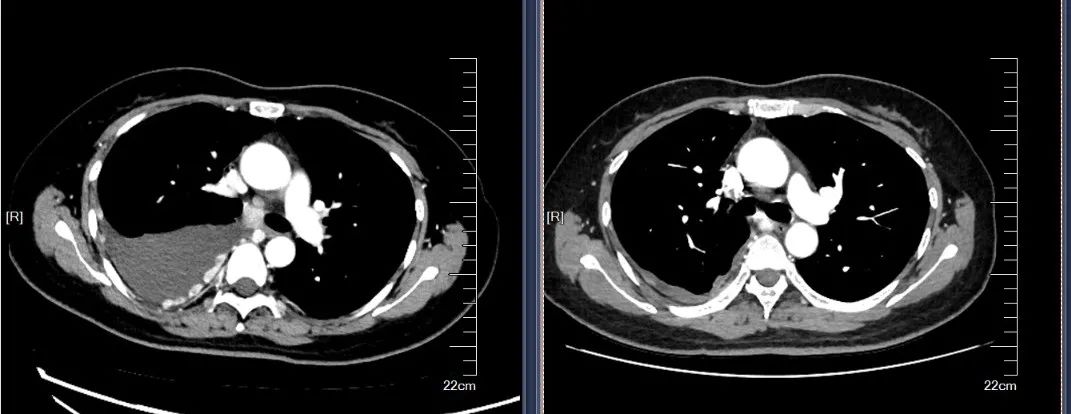

2020-05查胸部CT示:两肺胸膜多发结节。

2020-08行“新抗原纳米疫苗+PD-1抗体”治疗,完成新抗原纳米疫苗皮下注射,PD-1抗体治疗3次,没能控制疾病进展。CT提示右侧胸腔大量胸腔积液,两肺胸膜多发结节较前明显增多。

2020-10开始行PD-1抗体联合抗血管生成治疗3周期,顺铂60mg胸灌,继予红色诺卡氏菌细胞壁骨架600ug胸腔灌注2次。予红色诺卡氏菌细胞壁骨架200μg每周一次皮下注射6次。2020-11查CT胸水较前大幅减少,肿瘤标志物较前下降,原有咳嗽、胸痛症状减轻。

左图(2020-10-09), 右图(2020-12-22)